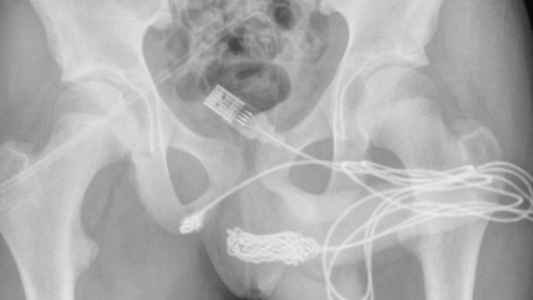

La asaltaron y le dejaron un hacha clavada en la cabeza: le salvaron la vida tras 4 horas de operación